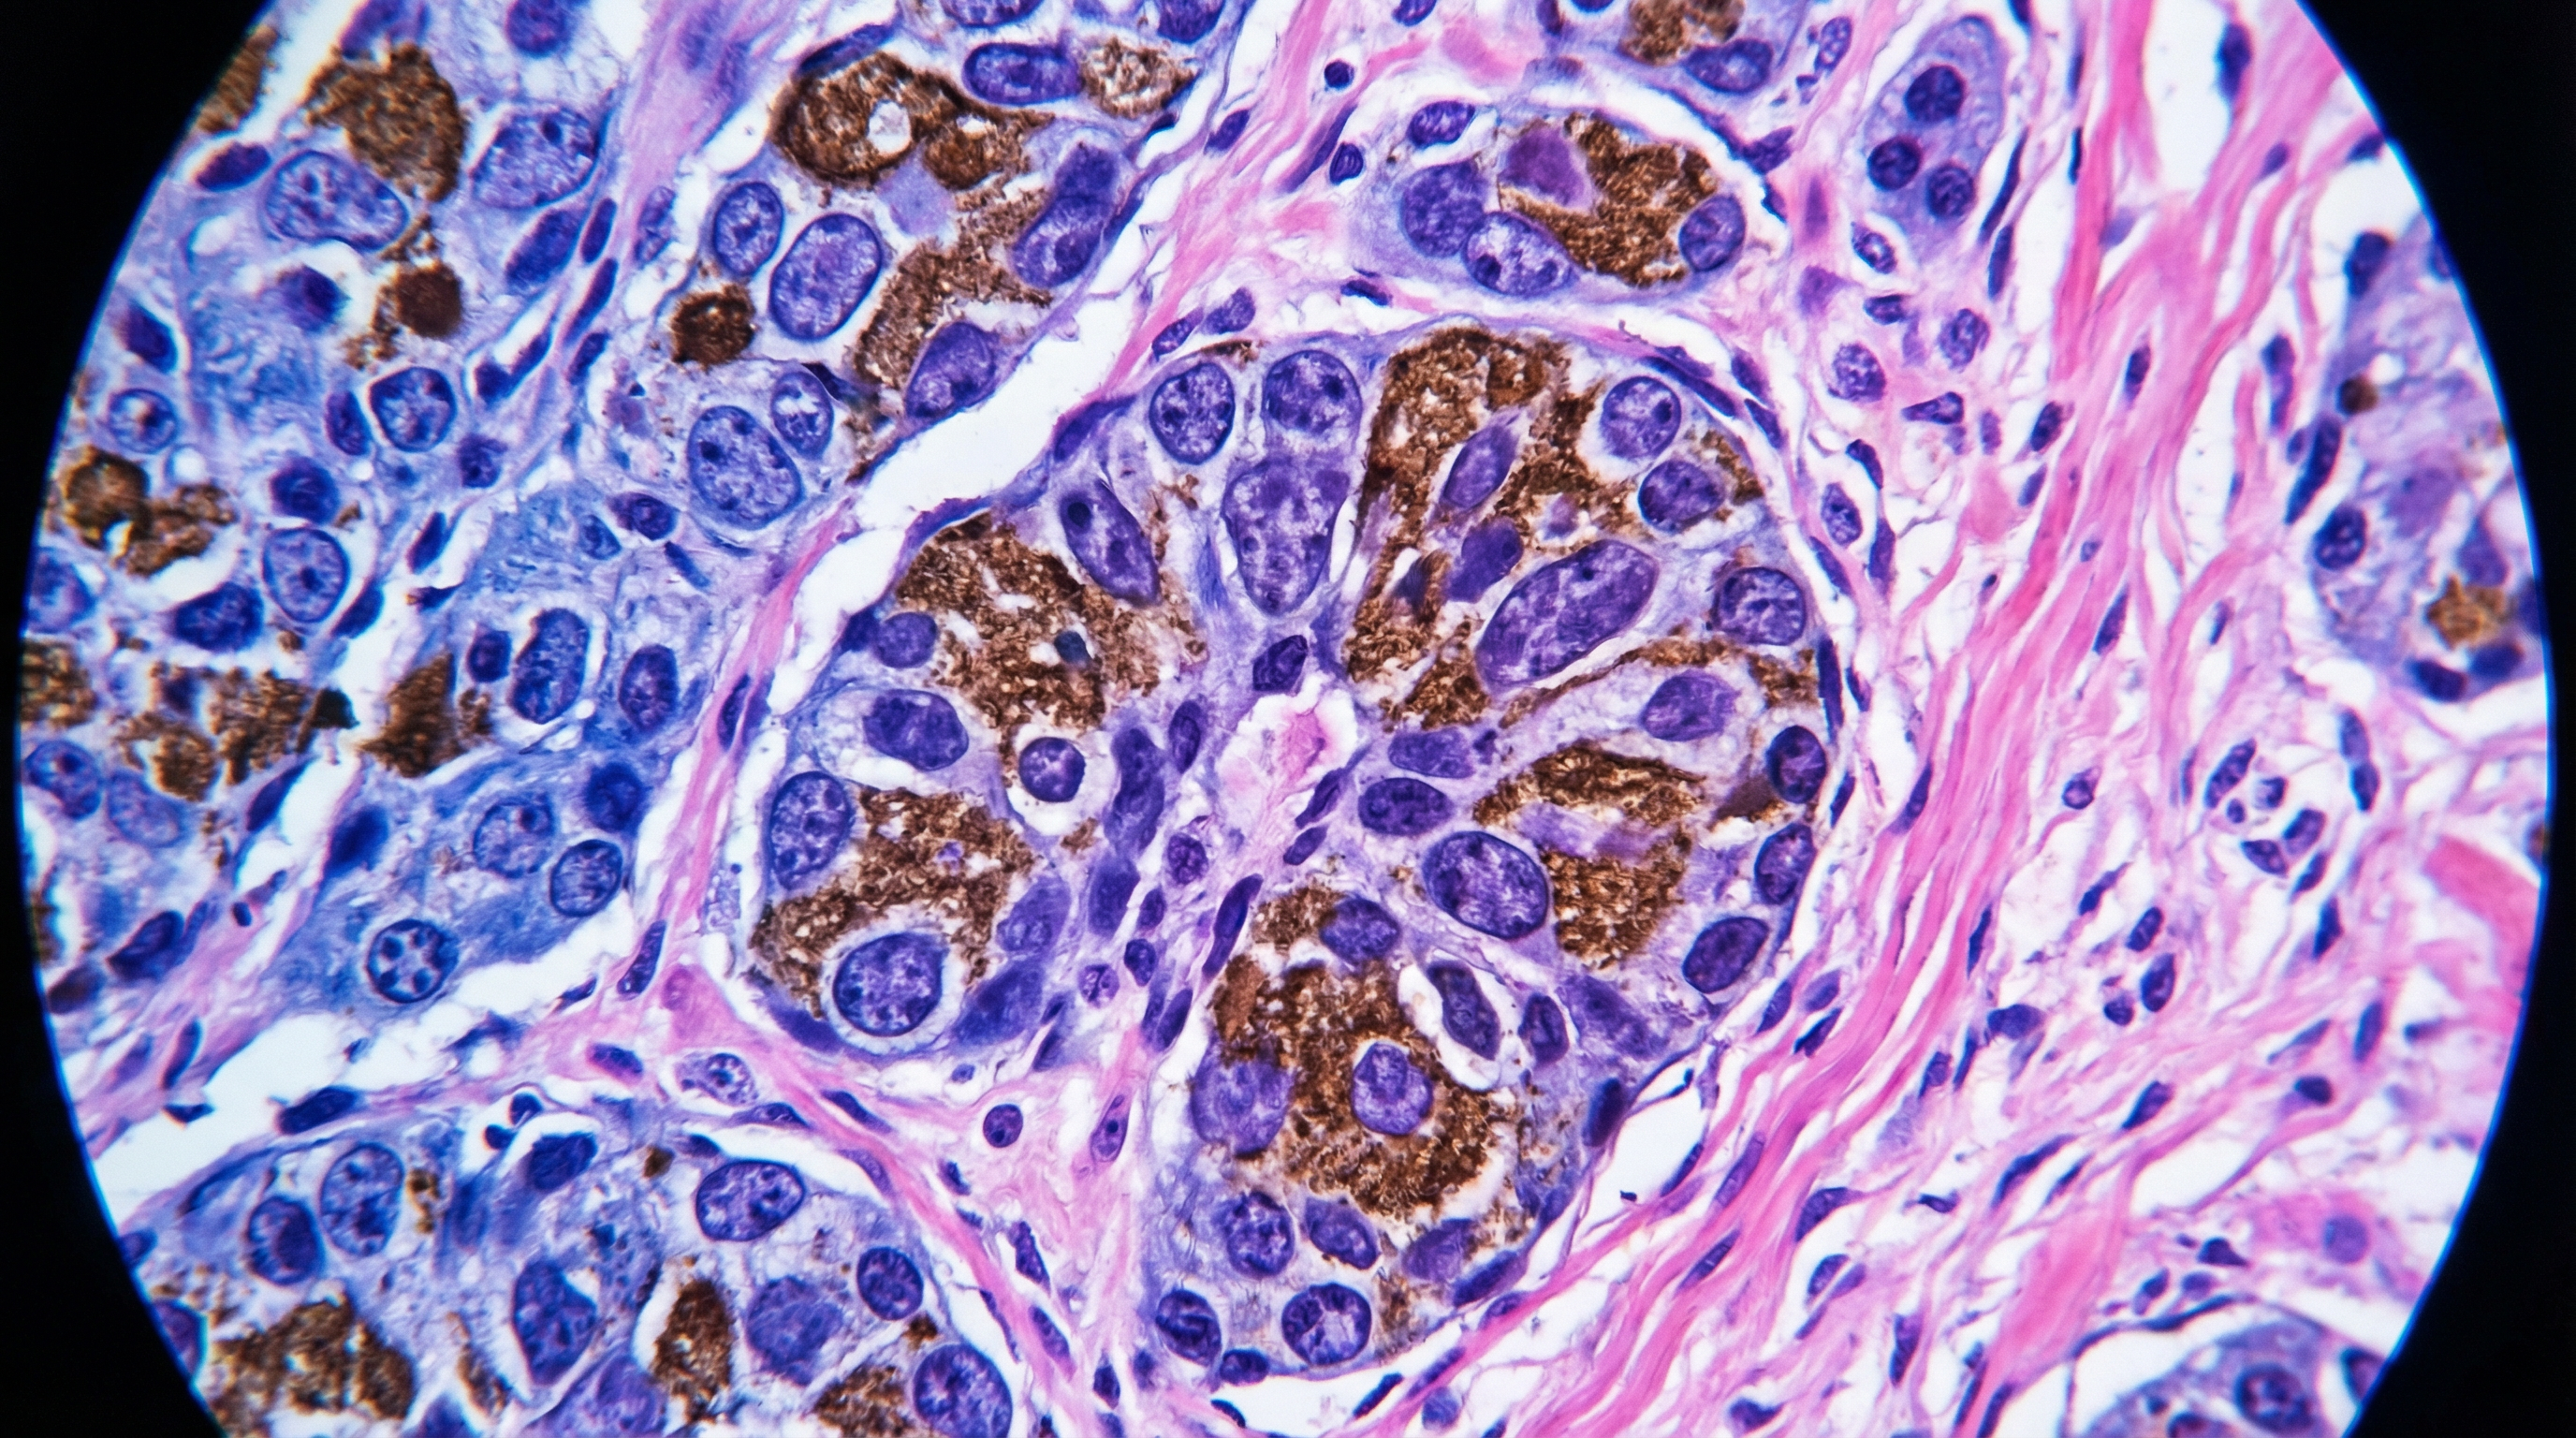

Melanoma histopathology digital pathology slide — AI in dermatology computational analysis

Digital Pathology & Computational Dermatopathology

Our ongoing work focuses on integrating foundation models with attention-based multiple instance learning on whole-slide images to extract prognostic signal invisible to the human eye.